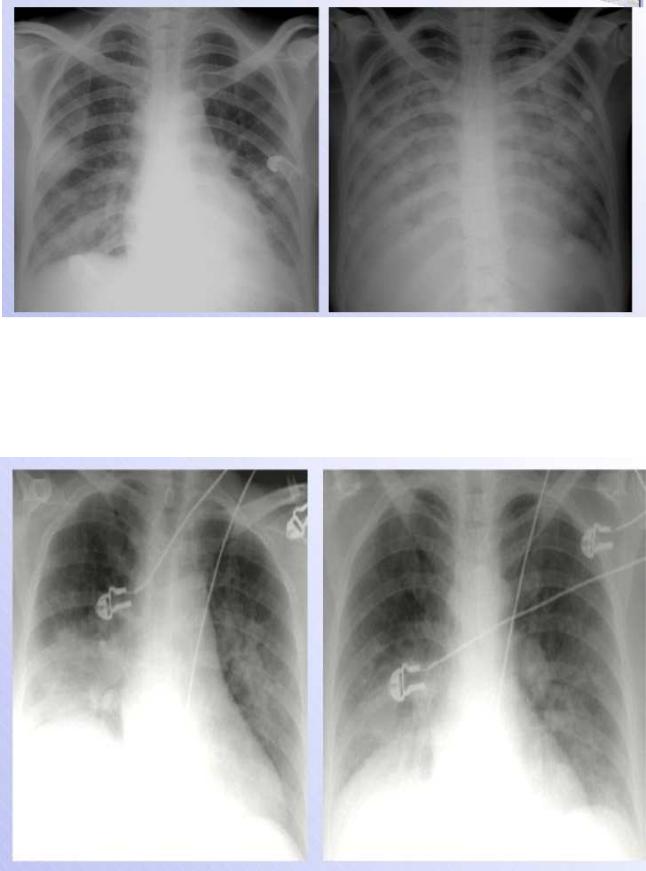

Chest x-ray should be performed in all patients (Fig.25 &26). Pulmonary venous congestion and interstitial or alveolar edema are characteristics of pulmonary edema. Kerley B lines reflect chronic elevation of left atrial pressure and chronic thickening of the intralobular septa from edema.

Fig.25. Heart failure

The upper zone bloo d vessels are distended and there are li near densities in the periphery of the lower z ones (interstitial or Kerley‘s B lines) a nd there are some areas of apparent co nsolidation, indicating alveolar pulmonary edema.

Fig.26 H eart failure following myocardial infarction.